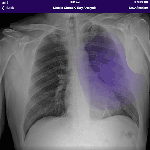

Mobile Chest X-Ray Analysis is an experimental project to showcase the offline Chest X-Ray model in Xamarin for Android and iOS. By leveraging AI technologies developed by the Microsoft Cloud AI Team we hope to increase the efficiency, accuracy, and speed with which radiologists can deliver diagnoses on 14 different chest conditions. In particular, our project can address the lack of radiologists available in developing countries by providing an alternate method of diagnosis for local doctors. Mobile Chest X-Ray Analysis showcases how developers can infuse AI into their own mobile applications.